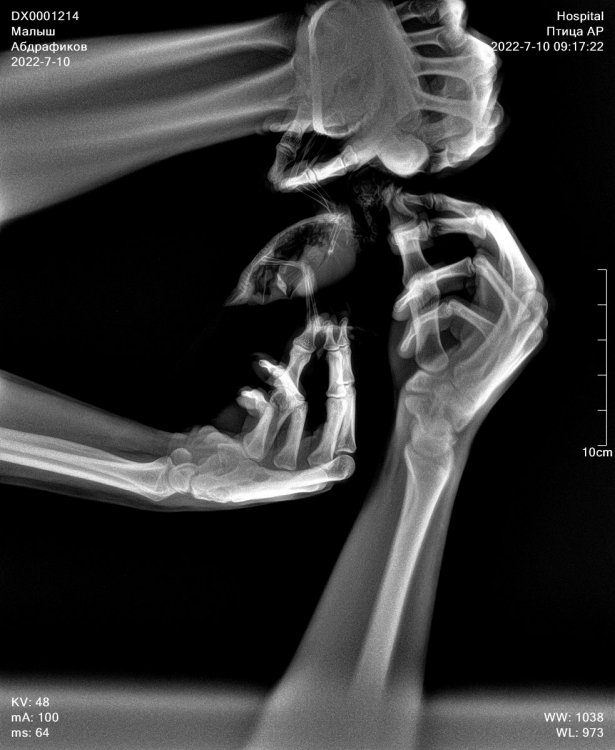

Добрый день ! Заболел попугай ,зовут Малыш, можно сказать заметили симптомы три дня назад. Первый день мотал головой и выкидывал круглые зерна (так понял рвота была ), повезли на следующий день на рентген , ветеринар сходу сказал что исход неблагоприятный и у него Мегабактериоз, выписал три препарата пить нистатин, флоконазол и антибиотик амфотерцин В суспензия ( но данного лекарства не нашли , и вроде как завоз запретили в Россию. Второй день пропал аппетит и почти перестал воду пить. Мы начали его кормить со шприца сами, делаем каши с фруктами , потому что сказали так кормить сейчас уже и лекарства давать как прописали (нистатин и флоконазол).Держим сейчас в клетки , так как есть ещё попугаи. Постоянно глаза закрывает и шатается , бывает дергает , держим под лампой нагревания. Вчера заметил что хочет корм кушать твёрдый , все ищет его , но ему как сказали нельзя сейчас . В общем ветеринару данному почему-то доверия нет , как нас встретил сходу и ничем толком не помог может сказать … просто сказал плохо все , есть дорогие препараты , но скорее всего не успеете начать лечить , как .. типо жить осталось пару дней . Так вот , хочу удостовериться в заболевание по рентген снимкам , если это возможно? Снимки на руках. Так же хотел узнать какая стадия заболевания? И что делать , если нет препарата одного в продаже , (антибиотика)? Очень жалко смотреть на своего попугая , осознавая что толком ничего непонятно и сделать мало что можем, кормим его , но после того как покормим , он как будто полуживой , запыхавшийся , так понял потому что вырывается . Он у нас особо не подпускает людей , так воспитали предыдущие хозяева

1.jpg

0.jpg